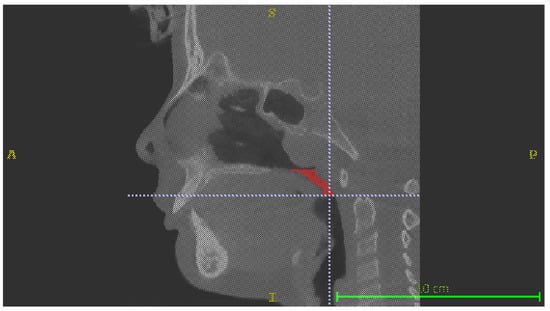

The CBCTs were used to perform digitized volumetric analysis using ITK-SNAP 3D segmentation software (Version 3.6.0, © 1998–2007, Paul A. Yushkevich, Guido Gerig). This software allows the user to select the space of the airways based on air radiological intensity values and then to delimit these spaces according to the anatomical landmarks considered, obtaining clear and precise limits. In this study, two volumes, delimited by a plane parallel to the Frankfurt plane, were defined and quantified:

Retropalatal volume (RPV), limited superiorly by a plane passing through posterior nasal spine and inferiorly by a plane passing through the most postero-inferior point of the soft palate (Figure 1);

Figure 1. Retropalatal Volume (RPV).